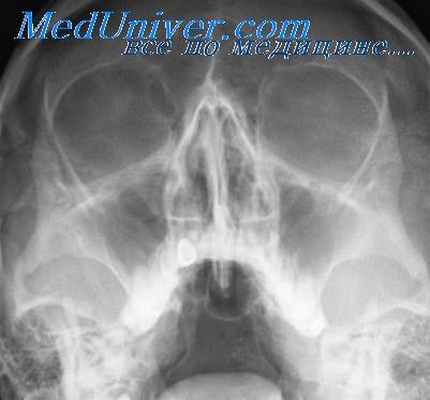

Всем пациентам с подозрением на этмоидит проводится риноскопия и эндоскопическое обследование носовых ходов и полости носа. Оценить строение решетчатой кости и степень ее воздушности помогает рентгенографическое обследование. В случае гнойного процесса хорошо определяется уровень жидкости (гноя) и его распространенность на все ячейки. Если это полипозный этмоидит, то хорошо видны патологические разрастания. Эта информация нужна для правильного планирования предстоящей операции.

Однако наибольшей диагностической ценностью обладает компьютерная томография. Это тоже рентгенологический метод, но в отличие от стандартной рентгенографии, он дает возможность послойно рассмотреть строение пазухи и выявить даже минимальные отклонения в ее состоянии.

Исходя из данных рентгенологического исследования больших контингентов больных хроническими синуитами, можно заключить, что изолированное хроническое воспаление клеток решетчатого лабиринта встречается редко. Чаще всего оно сопровождается поражением группы пазух с одной или с обеих сторон.

Хроническому фронтиту также нередко сопутствует этмоидит. Рентгеновская картина хронического этмоидита разнообразна п зависит от формы этого заболевания. Перед рентгенологом, производящим исследование больного с хроническим этмоидитом, неизменно возникает задача определения распространенности процесса и патологической формы заболевания.

По характеру затемнения области решетчатого лабиринта гнойную и гипертрофическую формы этмоидита обычно невозможно различить из-за малых размеров и большого количества накладывающихся друг на друга клеток. Тем не менее по некоторым симптомам можно установить различного характера изменения в тончайших костных стенках решетчатых клеток вплоть до их полного гнойного расплавления.

Гомогенный, бесструктурный характер затемнения решетчатого лабиринта при хроническом этмоидите может быть обусловлен рассасыванием костных балок вследствие длительного воспаления слизистой оболочки и костного мозга при часто наблюдающихся полипозных изменениях слизистой и образовании замкнутых полостей, заполненных гнойной жидкостью (пиоцеле) или слизью (мукоцеле).

Чтобы произвести полноценное рентгенологическое исследование всех отделов решетчатого лабиринта, нельзя ограничиться одной рентгенограммой в подбородочно-носовой проекции, с которой обычно начинают изучение рентгеновской анатомии и патологии придаточных пазух носа, так как для последних она является лишь обзорной проекцией.

Наибольшее значение для суждения о состоянии пазух решетчатой кости имеет лобно-носовая проекция, а специально для задних решетчатых клеток—полуаксиальная передняя и аксиальная задняя. Ценность последней заключается еще в том, что при полном разгибании головы раскрывается область всей решетчатой кости.

При описании рентгенограммы в указанных выше проекциях и установлении признака затемнения при хроническом этмоидите, который часто сопровождается односторонним или двусторонним поражением целой группы пазух, следует всегда учитывать феномен суммации теней и светов от анатомических деталей черепа, стоящих на пути центрального луча.

Так, при рентгенографии в лобно-носовой проекции в случае поражения передних решетчатых клеток может быть не замечен симптом понижения их прозрачности из-за стоящих на пути центрального луча хорошо развитых, нормально пневматизированных задних клеток решетчатого лабиринта. На снимке в аксиальной проекции при нормальном состоянии воздушности всех клеток решетчатой кости можно обнаружить одностороннее или тотальное затемнение в их области, обусловленное гипертрофией или полипозом слизистой оболочки полости носа.